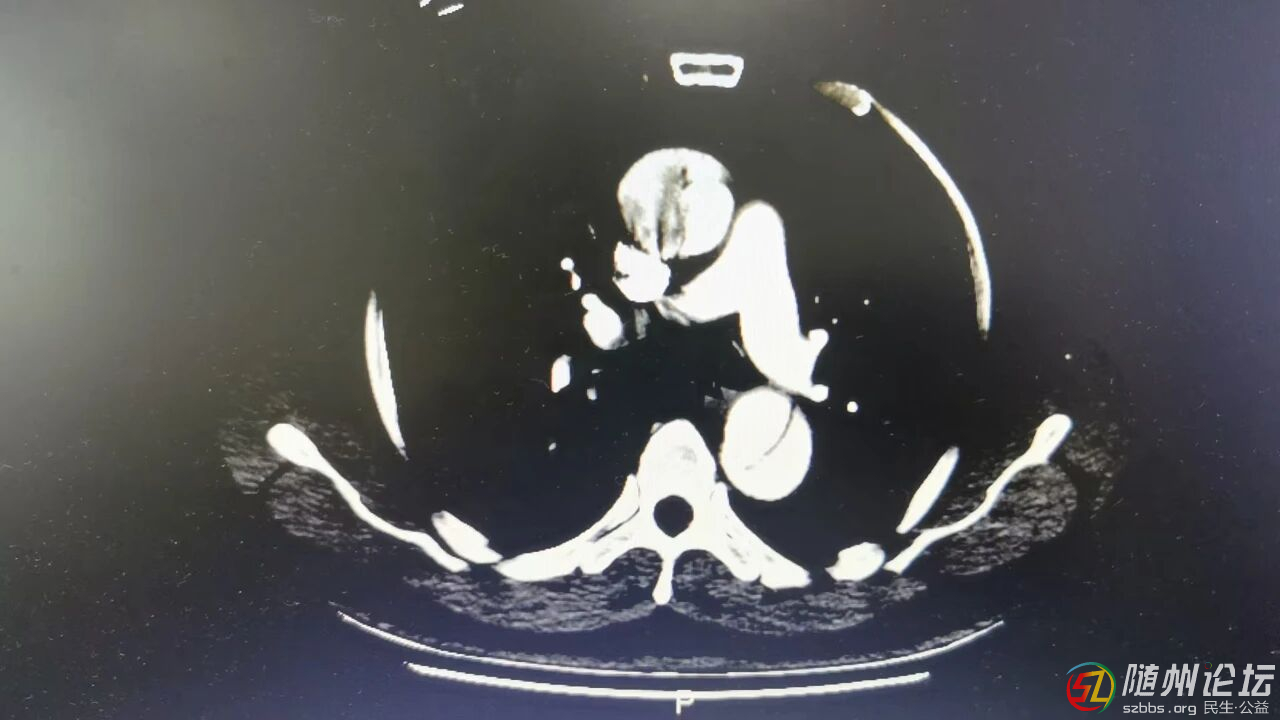

醫(yī)院急診科通過(guò)CT血管檢查,發(fā)現(xiàn)真正的元兇并非心梗,而是更為兇險(xiǎn)的“A型主動(dòng)脈夾層”,于是立即將他收治到心胸血管外科。